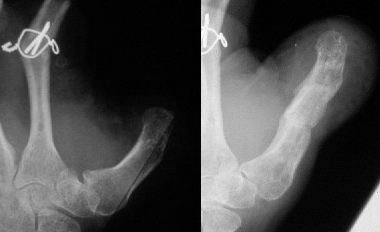

The initial lawnmower injury..

Treated with completion of the thumb amputation, external fixation of the distal radius fracture and primary metacarpophalangeal arthrodesis of the fingers.